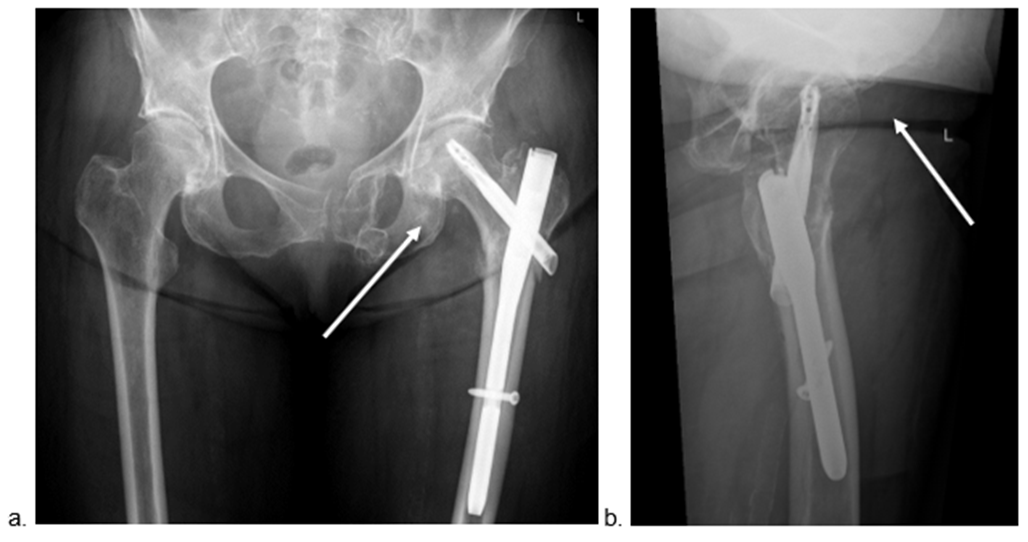

was uneventful and the patient was discharged after two weeks. However, five weeks postoperatively, she was readmitted because of acute onset of immobilizing pain in the left groin. Radiographs and CT imaging showed a migration of the lesser trochanter into the groin (Figure. 4 and 5).

Figure 4: Anteroposterior (a) and axial (b) radiographs 5 weeks postoperatively, showing the further proximal dislocation of the lesser trochanter up to the groin (circle and arrow)

Figure 5: Axial CT-scan 5 weeks postoperatively showing the exact position of the dislocated lesser trochanter directly anterior to the femoral head (arrow), causing the immobilising inguinal pain.

The patient was admitted for pain treatment and mobilization. Due to persistent, immobilizing pain, she underwent surgical resection of the displaced lesser trochanter through a direct anterior approach. The fragment could be identified with the help of intraoperative fluoroscopy inside the rectus femoris muscle just anterior to the hip joint. Resection of the fragment from the retracted iliopsoas tendon was performed. Postoperative radiographs confirmed the complete resection of the lesser trochanter (Figure. 6). Further hospital stay was uneventful and the patient regained immediate full weight-bearing mobility without pain. The follow up for three months after the revision surgery showed a fully recovered and mobile patient. Especially the flexion of the hip was symmetrical in terms of range of motion and strength compared to the contralateral side. The further radiographs up to 2 years postoperatively showed also an uneventful fracture healing with an optimally positioned implant.

Figure 6: Anteroposterior (a) and axial (b) radiographs after the revision surgery with the resection of the lesser trochanter via a direct anterior approach (arrows indicate the absence of the lesser trochanter).